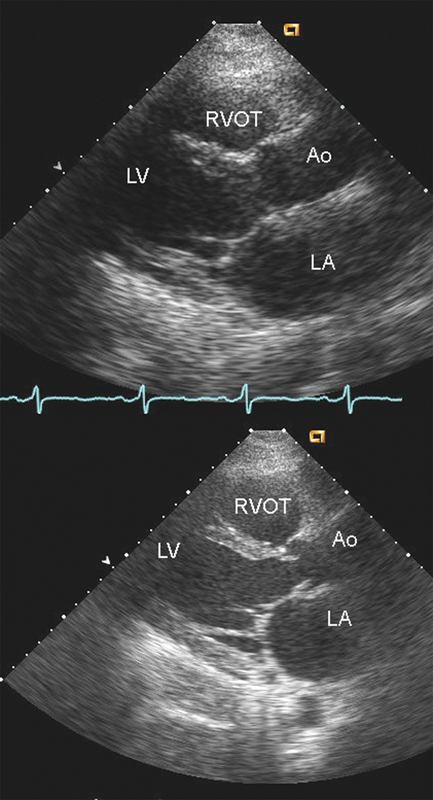

فحوصات تشخيصية لبعض امراض القلب والشرايين التاجية